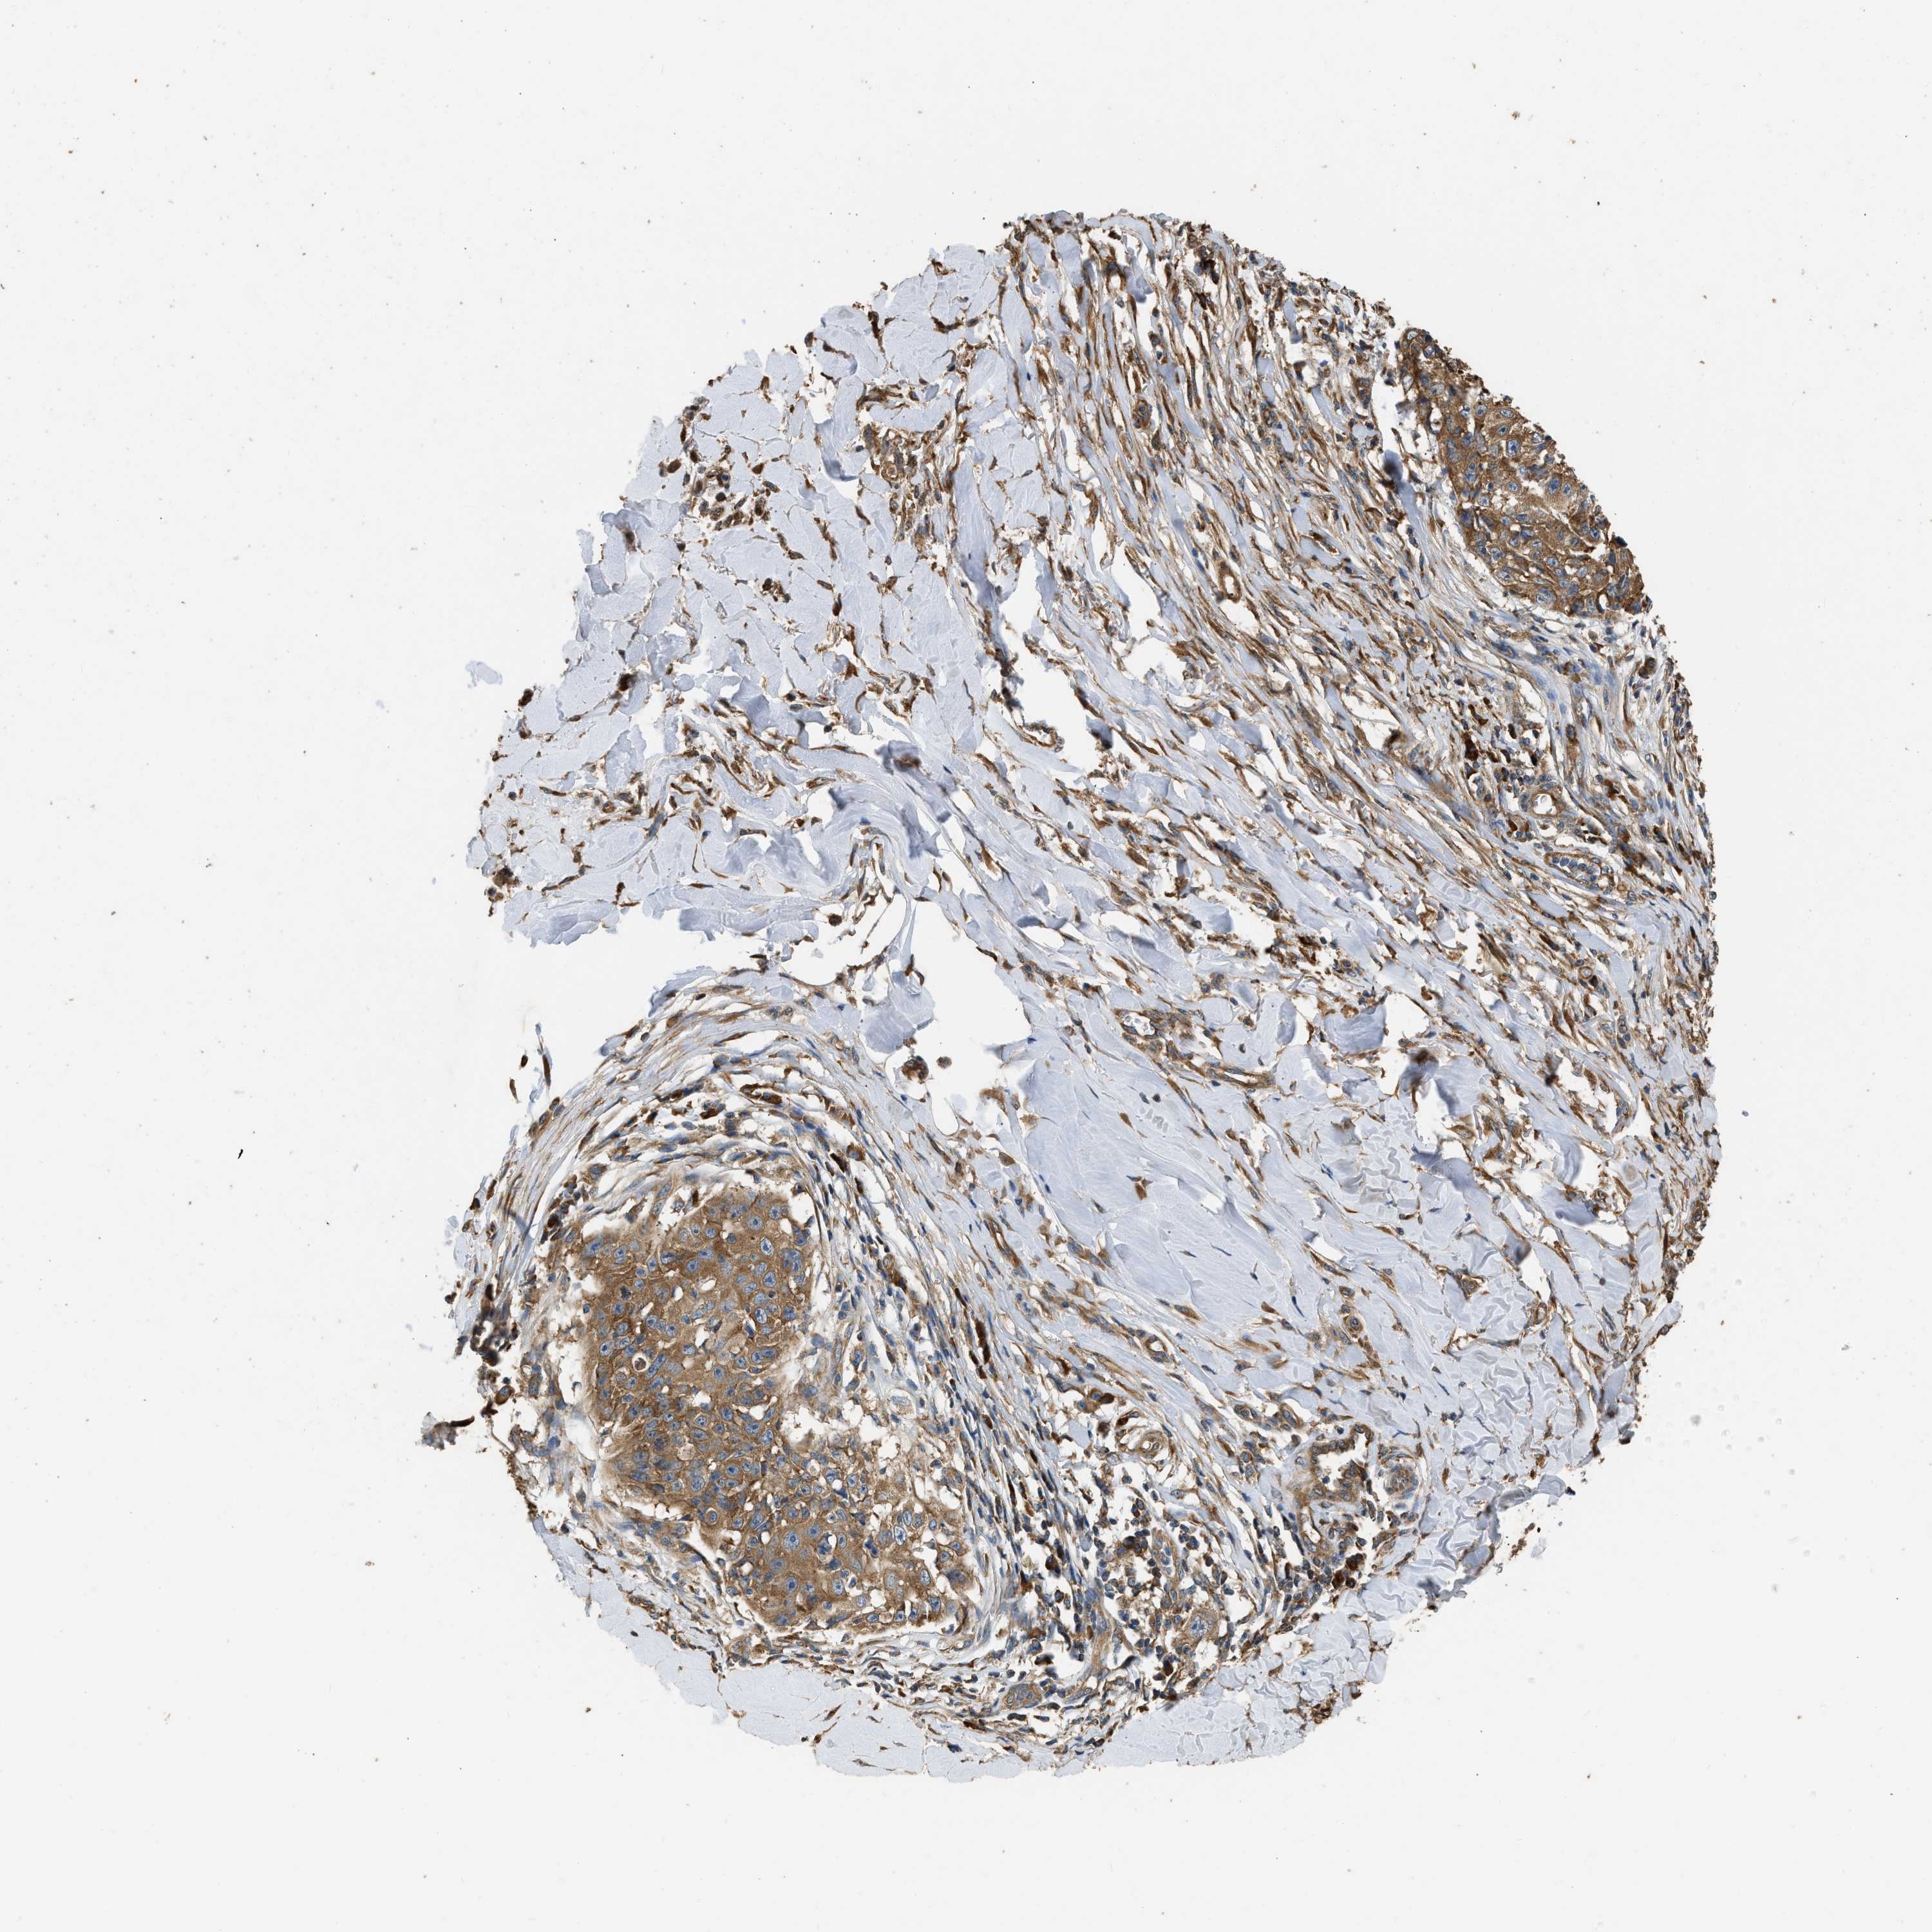

SKIN CANCER - Protein expressioni

A mouse-over function shows sample information and annotation data. Click on an image to view it in a full screen mode. Samples can be filtered based on level of antibody staining by selecting one or several of the following categories: high, medium, low and not detected. The assay and annotation is described here.

Each image is clickable and will lead to virtual microscopy that enables deeper exploration of all samples and also displays staining intensity scores, fraction scores and subcellular localization as well as patient and tissue information for each sample.

Antibody HPA017887

Staining

High

Intensity

Strong

Quantity

>75%

Location

Nuclear

Squamous cell carcinoma in situ, NOS

Squamous cell carcinoma, NOS

Squamous cell carcinoma, metastatic, NOS

Basal cell carcinoma